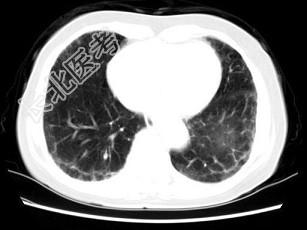

- 单项选择题女,35岁, 咳嗽,咳痰, 发热3月余,胸部CT如图, 最可能的诊断为 ( )

A、类风湿肺炎

B、红斑狼疮性肺炎

C、间质性肺炎

D、肺结节病

E、肺部感染